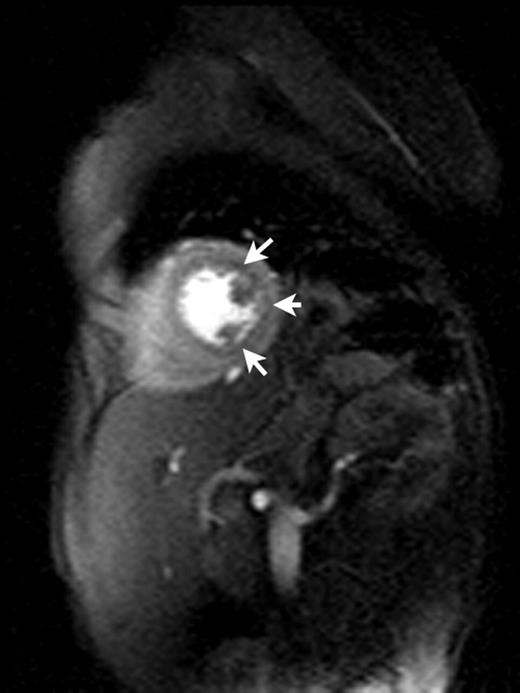

Results. Three subjects, all SS genotype, had striking subendocardial ischemia (top image, arrows) with vasodilator stress that was not present at rest (signal intensity-vs-time curves, solid line=abnormal subendocardium, dotted and dashed=normal myocardium, dot-dash=blood pool). Myocardial T2* was normal in all subjects (25 to 33ms) as were DME, LV mass and LVEF. One subject with pulmonary hypertension had marked RV dysfunction (RVEF 26%). No subject had obstructive epicardial coronary disease, though proximal coronary diameters were significantly larger for SCD patients compared to controls (2.7mm/m2 versus 1.9mm/m2, p<0.001).